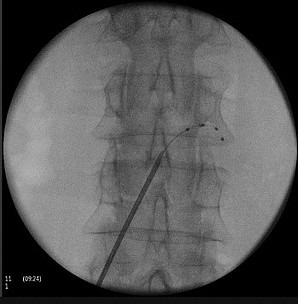

Rückenmarksstimulation

Vor allem bei bestimmten Schmerzsyndromen, die nicht oder nicht mehr ausreichend auf eine medikamentöse Therapie ansprechen, ist es möglich, durch die Rückenmarksstimulation eine Schmerzlinderung zu erzielen. Hierbei werden feine Elektroden in den Rückenmarkskanal eingesetzt, die elektrische Impulse abgeben. Das Einbringen der Elektroden kann in örtlicher Betäubung erfolgen. Die Elektroden werden durch einen Impulsgeber angesteuert, der unter die Haut am Gesäß oder an der Bauchwand der Patient:innen implantiert wird. Die abgegebenen elektrischen Impulse hemmen die Schmerzweiterleitung. Die Schmerztherapie durch Rückenmarksstimulation findet Anwendung nach Verletzung von Nerven oder des Rückenmarkes, aber auch bei Phantomschmerzen und bei behandlungsresistenten Schmerzen durch Durchblutungsstörungen bei Herzkrankheit (Angina Pectoris) und Gefäßkrankheit der Beine (pAVK). Bei der Gefäßkrankheit der Beine (pAVK) kann die Stimulation zudem dazu beitragen, die Durchblutung wieder zu verbessern und die Gliedmaßen zu erhalten. Die Nervenstrukturen bleiben bei der Rückenmarksstimulation erhalten, sodass die Stimulation jederzeit rückgängig gemacht werden kann. Die Einstellungen des Impulsgebers lassen sich von außen – auch durch die Patient:innen – verändern, sodass die Stimulation jederzeit an die Bedürfnisse der Patient:innen angepasst werden kann.